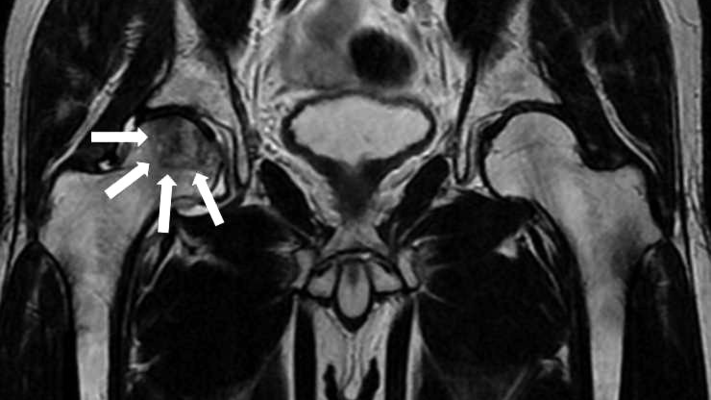

消化器内科医 加藤則廣氏食べ物をうまく飲み込むことができない状態を嚥下(えんげ)障害と呼びます。嚥下障害を来す病気には食道がんや咽喉頭がんなどの悪性疾患がありますので、早めの医療機関に受診が必要...